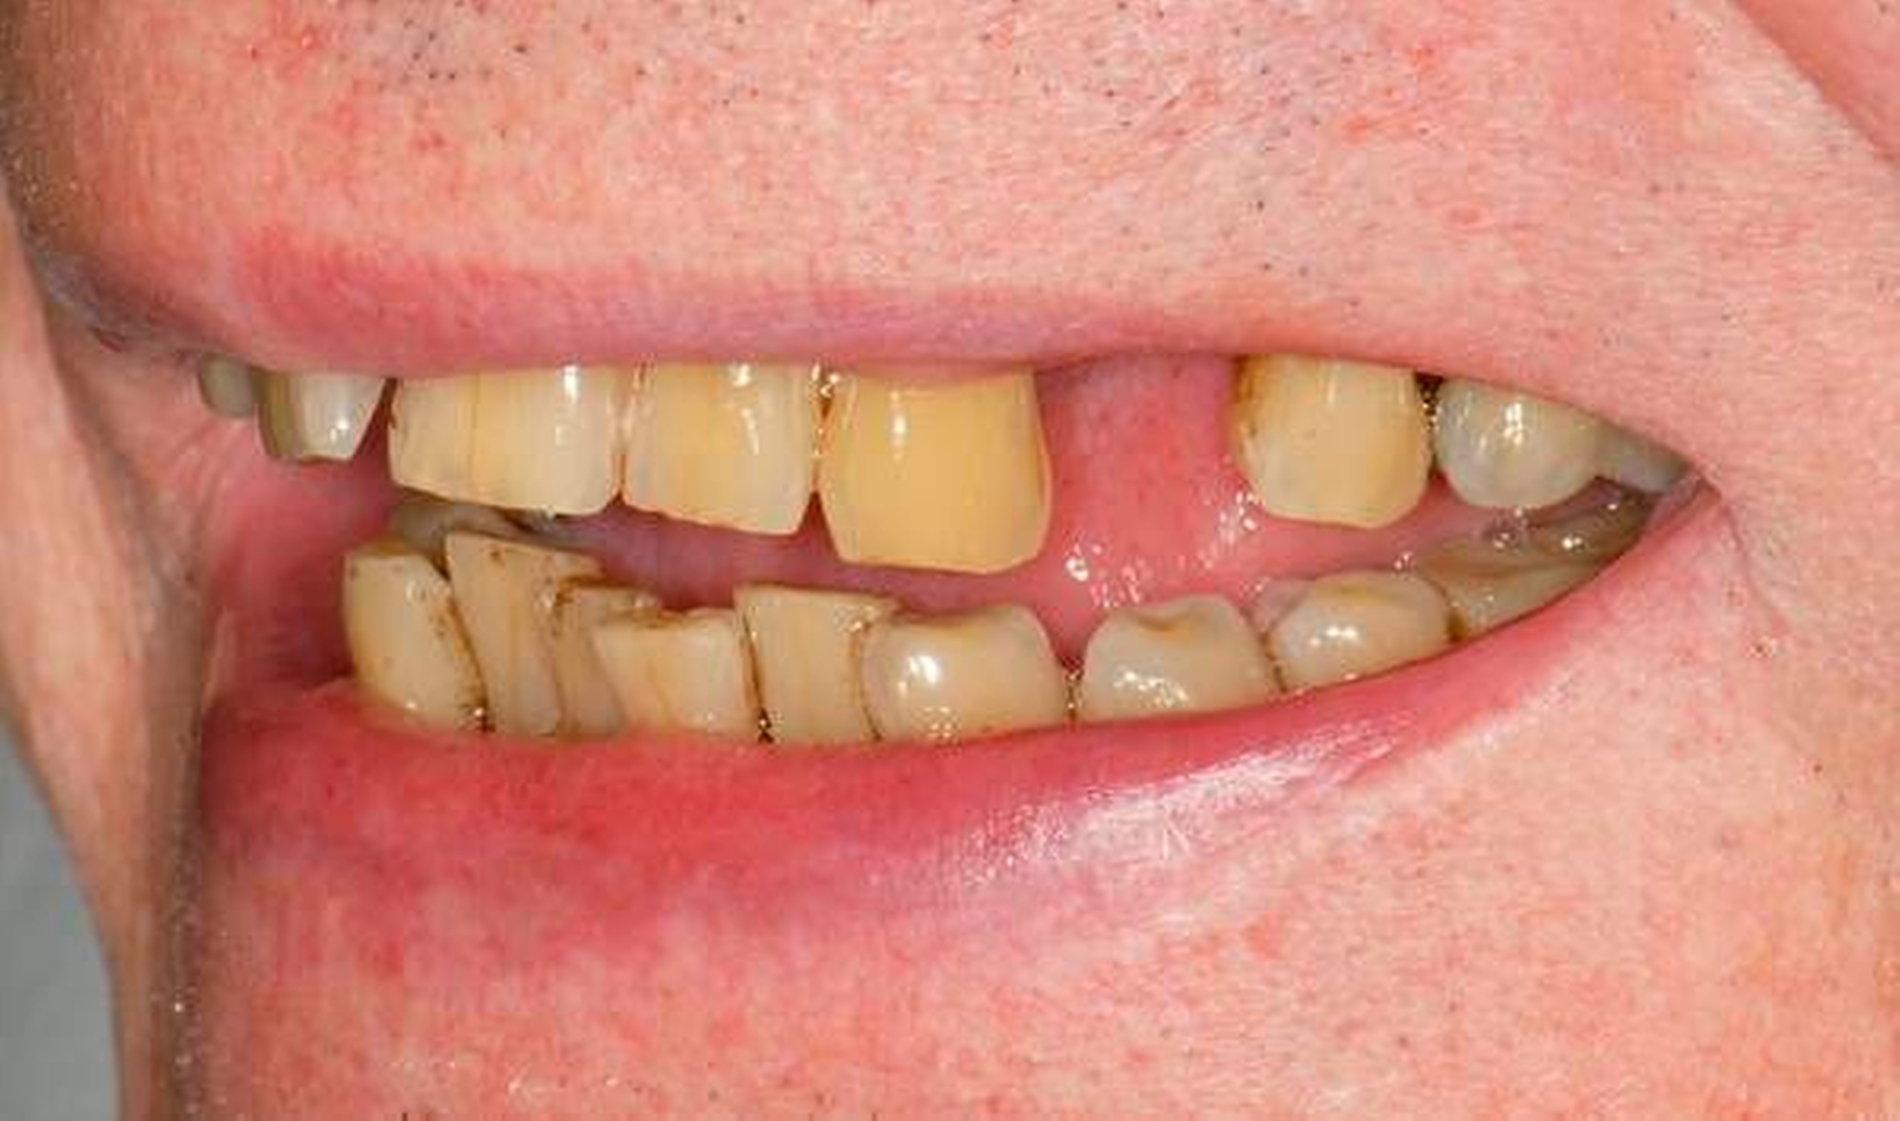

Abbildung 1a bis 1f: Direkte Überkronung im Frontzahnbereich (R1-Technik)

In den Abbildungen 1 bis 3 werden Optionen für frugale Interventionen auf restaurativem Sektor aufgeführt. Es handelt sich um direkte Vollüberkronungen im Frontzahnbereich (hier: hergestellt in R1-Technik / einphasig) (Abbildung 1), direkte Teilüberkronungen im Seitenzahnbereich (hier: hergestellt in R1-Technik / einphasig) (Abbildung 2), Reparatur-Restaurationen im Seitenzahnbereich (hier: hergestellt in R2-Technik / zweiphasig) (Abbildung 3). Technische Einzelheiten zur Vorgehensweise und den Ergebnissen sind an anderer Stelle beschrieben (Literatur siehe oben).

Am Beispiel von Abbildung 1 (stark zerstörte Zahnkrone eines Schneidezahns) kann das Prinzip der frugalen Intervention erläutert werden:

Früher wurde für die hier beschriebene Ausgangssituation folgendes Procedere gewählt:

Wurzelkanalbehandlung des vitalen Zahns als Voraussetzung für eine Stiftversorgung

Einsetzen eines Wurzelkanalstifts

Einsetzen einer indirekt gefertigten Stiftkrone

Durch die Erfolge der Adhäsiv- und Komposittechnik kann heute folgendermaßen vorgegangen werden:

Verzicht auf Wurzelkanalbehandlung / Erhaltung der Vitalität des Zahns

Verzicht auf Wurzelkanalstift

direkte minimalinvasive Kompositkrone (Verzicht auf indirekte Vorgehensweise)

Die potenziellen medizinischen und ökonomischen Vorteile dieser frugalen Intervention sind vielfältig:

Schonend: Die oralen Strukturen werden geschont und die Versorgung ist hinreichend stabil. Durch den Verzicht auf Wurzelkanalstifte wird das Wurzelfrakturrisiko reduziert. Zudem können Material-, Geräte- und Personalressourcen aus Praxis und Techniklabor, die beim klassischen Vorgehen anfielen, reduziert werden.

Bezahlbar: Hier ist anzumerken, dass die Kosten unter anderem von der zahnärztlichen Expertise abhängig sind: Zahnärzte, die mit direkten Restaurationen große Erfahrung haben, können zügiger und mit besserem Erfolg arbeiten als Kollegen mit geringerer Erfahrung auf diesem Gebiet; die Behandlung ist gleichwohl anspruchsvoll und deshalb nicht „billig“. Eine direkte Vorgehensweise kann, muss aber nicht automatisch zeit- und kostensparender sein als eine Versorgung mit indirekt hergestellten Werkstücken.

Gut genug: Ästhetische Feinheiten lassen sich bei direkten Restaurationen nicht immer in gleicher Perfektion einarbeiten wie bei indirekt gefertigten Kronen, auch die Stabilität des Hochglanzes lässt bei einigen Kompositpräparaten noch zu wünschen übrig. Andererseits erlauben die direkten Verfahren inzwischen mitunter sehr flexible Vorgehensweisen, die sich auch mit Farb- und Formkorrekturen von Zähnen kombinieren lassen. Die Erwartungen eines großen Teils der Patienten werden hinreichend erfüllt und die Nutzen-Risiko-Relationen wie auch die Aufwand-Kosten-Relationen erscheinen – wenn auch nicht durchgängig – so doch zumindest in vielen Fällen günstig.